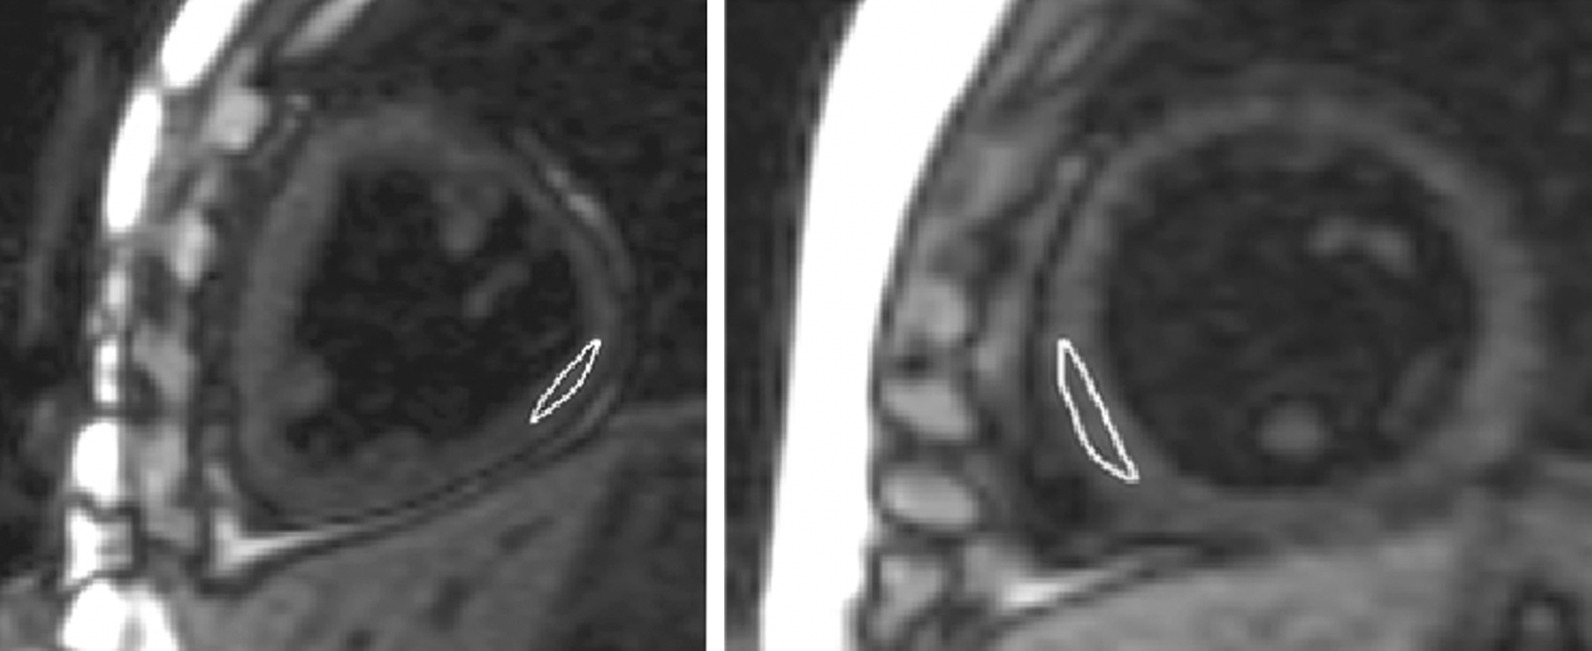

T1 relaxometry analysis was performed by a single observer (CdL) with 10 years of CMR experience on the online motion-corrected source images, using’Qmap 2.2.36’ (Medis Medical Imaging Systems). Regions of interest (ROIs) were drawn in the freewall of the dominant ventricle, propagated to each of the eight source images and adjusted for motion (Fig. 1). In controls, T1 was measured in the entire left ventricular myocardium. Only the central third of the myocardium was included in order to avoid partial-voluming with blood or epicardial fat. Areas of LGE were excluded from T1 ROIs. Extracellular volume (ECV) was calculated with patient’s hematocrit and the pre- and post-contrast T1 values [16]. To assess the reproducibility of myocardial T1 measurements, a random sample of 20 patients was re-measured by a second observer (MR) after several months of full-time training in postprocessing. For intra-observer variability the same observer re-measured T1 and ECV on the same sample. All measurements were completed under the supervision of a CMR staff (LGW) with 15 years of CMR experience.

Fig. 1.

Frame from the modified Look-Locker inversion recovery acquisition in short axis orientation. Myocardial T1 measurements in Fontan patients with a dominant right (right) and a left ventricle (left). Regions of interest were drawn in the free wall of the dominant ventricle